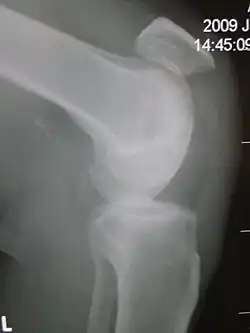

| Patellar tendon rupture showing a marked distance between the tibial tuberosity and the bottom of the knee cap. | |

Patellar tendon rupture can usually be diagnosed by physical examination. The most common signs are: tenderness, the tendon's loss of tone, loss of ability to raise the straight leg and observation of the high-riding patella. Radiographically, patella alta can be detected using the Insall and Salvati method when the patella is shorter than its tendon. Partial tears may be visualized using MRI scans.[4]